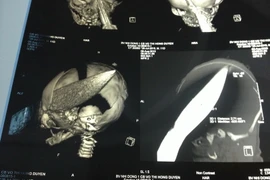

Cấp cứu kịp thời bệnh nhân bị vật sắc đâm thấu buồng tim ảnh 1(Ảnh minh họa: Dương Ngọc/TTXVN)

Trước đó, khoảng 19 giờ ngày 19/8, bệnh nhân Nguyễn Văn Phú được đưa đến Bệnh viện đa khoa khu vực Định Quán trong tình trạng bị một vết thương sâu ở ngực trái. Vì mất rất nhiều máu nên bệnh nhân ở trạng thái lơ mơ, da xanh, vã mồ hôi, thở ngáp, mạch nhanh nhẹ khó bắt, huyết áp không đo được (60/40 mg Hg qua monitor), nhịp tim khó nghe. Sau khi tiến hành hồi sức chống choáng và làm các xét nghiệm cơ bản, các bác sỹ nhận định bệnh nhân Phú bị sốc mất máu, buồng tim bị vật sắc đâm thấu.

Đến gần 21 giờ cùng ngày, các bác sỹ tiến hành phẫu thuật tối khẩn cấp cho người bệnh. Trong quá trình phẫu thuật, ê kíp bác sỹ phát hiện bệnh nhân Phú ngoài bị sốc mất máu, thủng buồng tim còn đứt động mạch gian sườn. Để hoàn thành ca mổ, bệnh nhân đã được truyền 8 đơn vị máu.